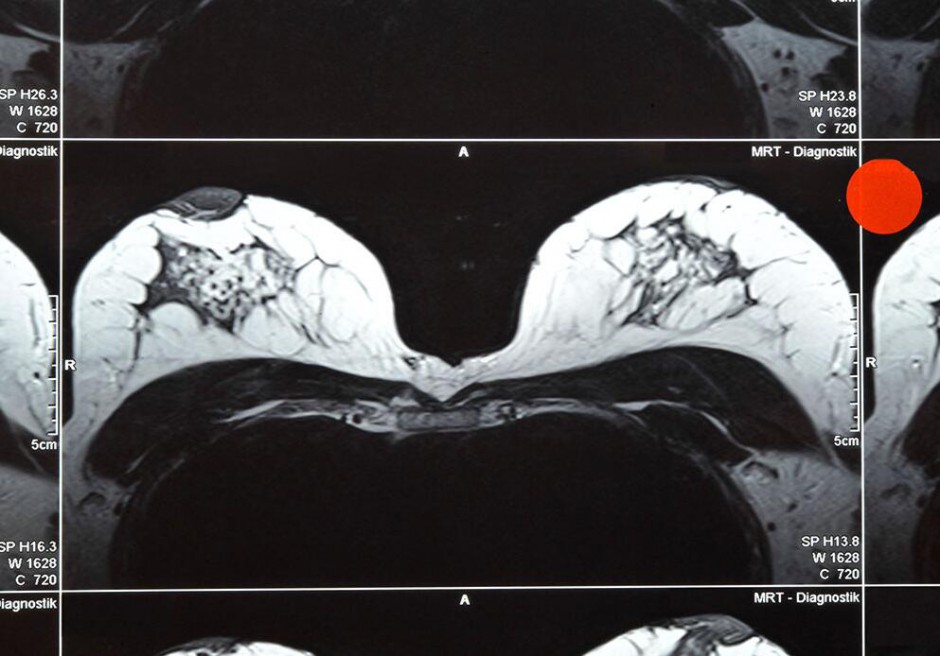

乳腺磁共振的作用

MR由于在乳腺疾病診斷中的高敏感性可以發(fā)現(xiàn)乳腺內(nèi)3mm左右的病灶,而且無電離輻射的優(yōu)點(diǎn),在國(guó)外已廣泛用于乳腺疾病的篩查和診斷。但如何選擇適當(dāng)?shù)娜橄贆z查時(shí)間窗顯得至關(guān)重要。

女性乳腺的血液循環(huán)是隨著激素的變化而進(jìn)行的,其結(jié)果造成在乳腺檢查中所使用的造影劑隨著月經(jīng)周期中的不同階段而發(fā)生變化,而這種影響在月經(jīng)的第二周最低,在月經(jīng)的第一周和第四周最高。所以乳腺的MR檢查最佳的時(shí)間窗選擇是在月經(jīng)完后的第二周,其次是第三周,而盡量避免在第一周和第四周進(jìn)行乳腺M(fèi)R檢查。